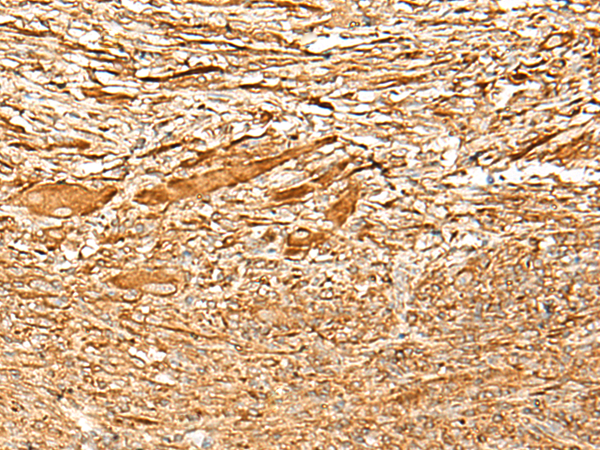

IHC positive control: |

Human liver cancer |